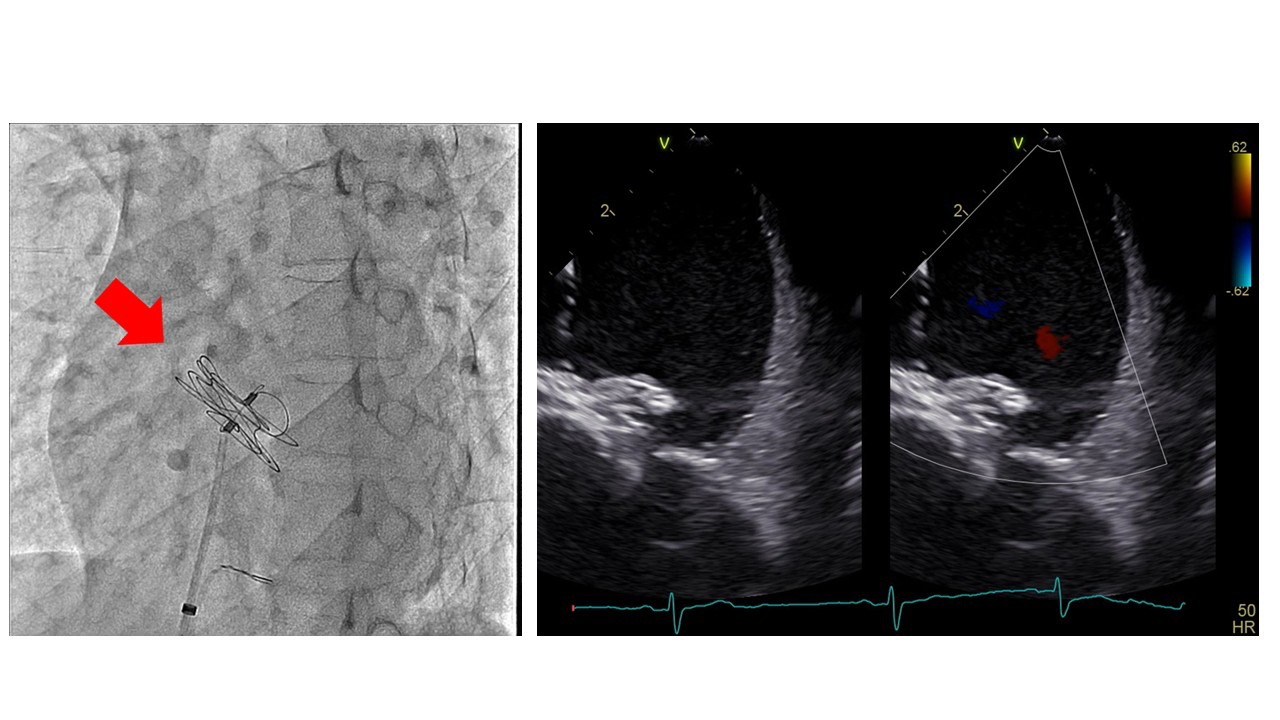

The patient underwent percutaneous ASD closure with local anesthesia. We confirmed the defect size with intracardiac echo (ICE) and a sizing balloon which showed 15.1mm. Thus, we chose GORE Cardioform ASD (GCA) Occluder 37mm according to the sizing chart.

The GCA was deployed as usual with fluoro and ICE images. However, the device gradually began to move inappropriately, and we understood it hadn¡¯t been deployed properly. Thus, we decided to retrieve and change the device. At first, we tried to retrieve it still attaching the atrial septum using standard EN snare, and caught the lock loop to remove from the atrial septum, however it came off the snare catheter because of weak locking loop wire. Next, we caught the floating device in right atrium with biopsy forceps and succeeded to pull it down to the iliac vein. Unfortunately, we could not move the occluder into the sheath, as its slippery designed hub and bulky device body even using combination of snare with biopsy forceps. Finally, we decided to insert 16 Fr. size sheath to use Crocodile Forceps for surgical gallbladder operation like laparoscopic cholecystectomy as its powerful gripping force.